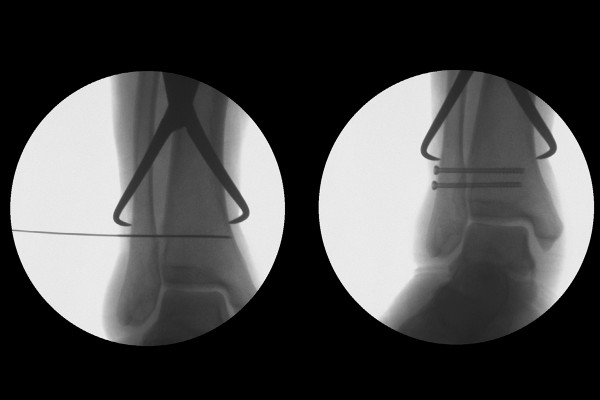

실시간 X-RAY인 C-ARM을 통해 확인하면서 수술을 진행합니다. 벌어진 경골과 비골을 클램프로 조여준 다음에, 원위경비결합인대가 잘 회복될 수 있도록 스크류 고정을 진행합니다.